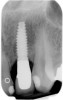

Figure 1  Radiograph demonstrating retained excess cement on abutment (see arrow).

Figure 1